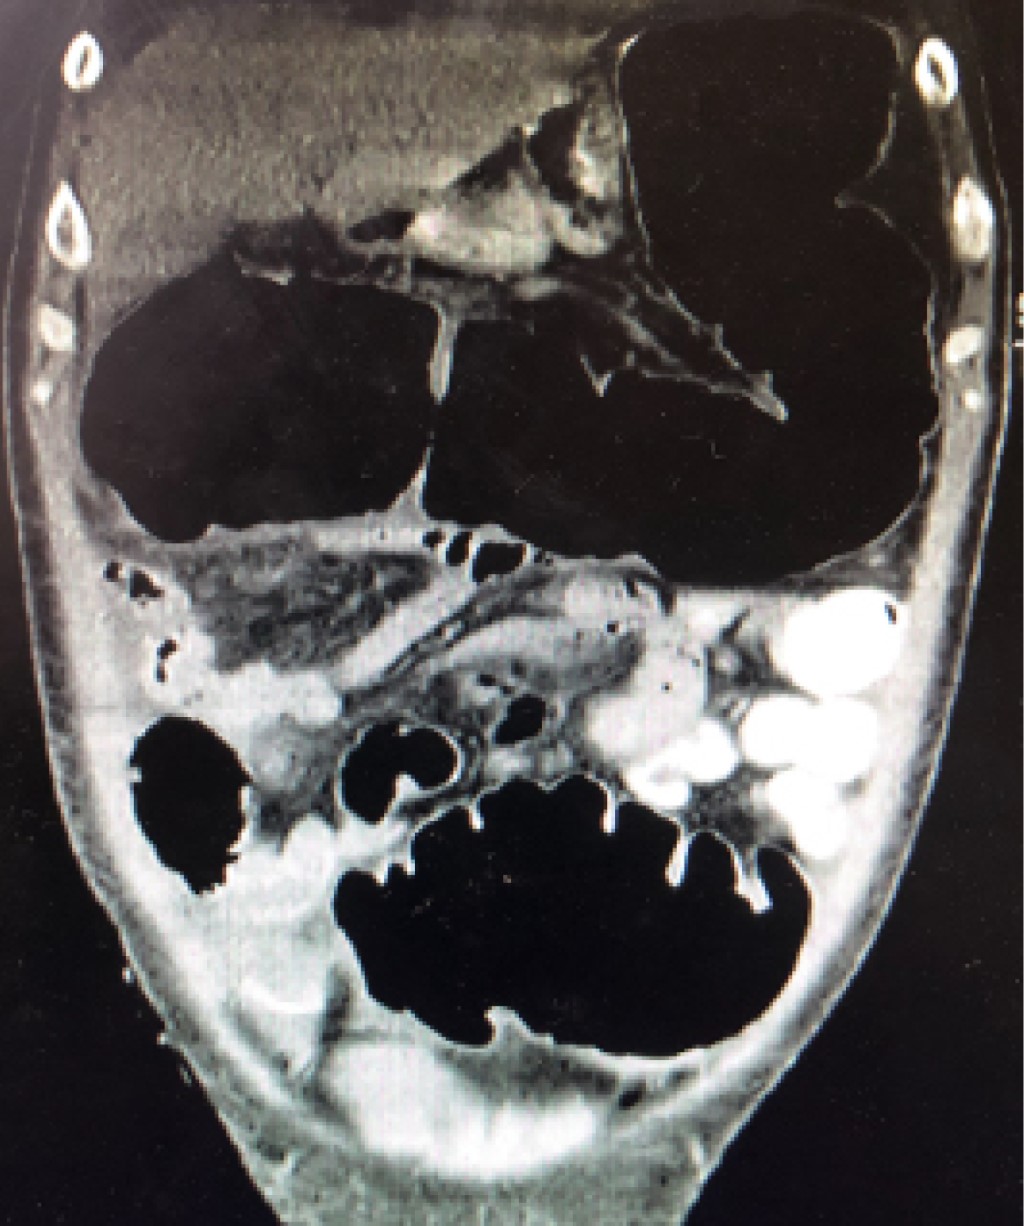

Figure 1